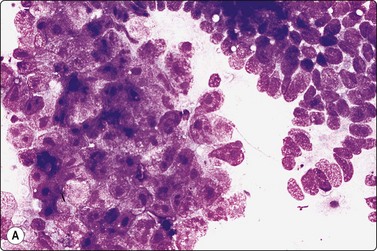

Tumors of more than one histologic type (mixed forms) (Figs 13.35 and 13.36)14,60,63,65

While the basic GCT types are infrequent in pure forms they are very frequent in mixed forms. Embryonal carcinoma and teratoma are each present in 47% of cases, and yolk sac tumors in 41%; 40% of TGCT contain varying numbers of syncytiotrophoblastic cells.12

image

Fig. 13.35 Tumor of more than one histological type (mixed form)

Large bisected tumor occupying most of the enlarged testicle in a male 19 years of age. Note hyalinized, degenerate and cystic areas.

image image

Fig. 13.36 Tumor of more than one histological type (mixed form)

(A) Well-differentiated glandular epithelium (right), large malignant cells similar to embryonal carcinoma (left) (MGG, HP); (B) Corresponding tissue section (A, H&E, IP; B, PAP, IP).

Criteria for diagnosis

Cellular aspirates; necrosis and hemorrhage frequent,

Three-dimensional clusters of epithelial malignant cells as described above

Coexisting teratomatous structures represented by mature or immature tissues originating from one or more blastodermal leaf: fusiform naked nuclei embedded in a myxoid background resembling embryonal mesenchyme; islets of cartilage; sheets of epithelial cells, which may be squamous, ciliated or intestinal (with goblet cells); bundles of fusiform cells with blunt ends reminiscent of leiomyoma; tight clusters of deeply stained bare nuclei may correspond to primitive neuroectodermal tissue.

The diagnosis of mixed forms is simple when malignant elements of an epithelial nature coexist with clear-cut teratomatous structures. Necrosis may obscure the neoplastic cells and the teratomatous component may be only minor or even absent. This can be explained by its greater cohesion causing under-representation in FNA samples. As a result, the differential diagnosis between mixed TGCT and embryonal carcinoma is sometimes difficult or impossible.14,59-61,65,66 The presence of multinucleated syncytial cells is not diagnostic of choriocarcinoma.